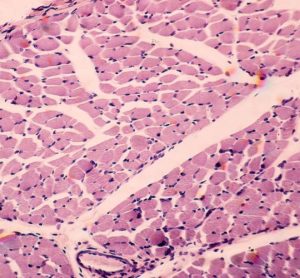

But phase II data of the small molecule inhibitor for Charcot-Marie-Tooth disease Types 1 and 2 did show it meeting secondary endpoints for functional improvements.